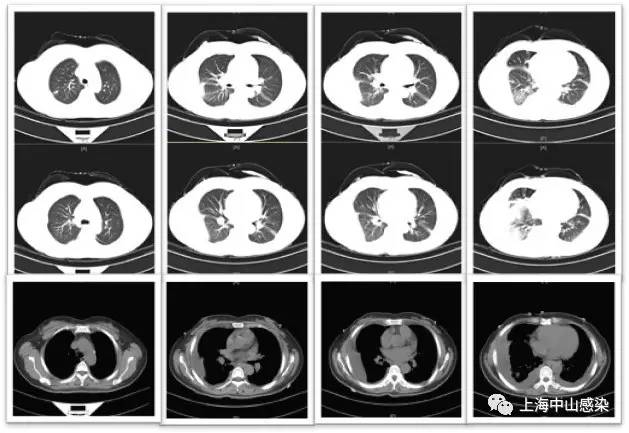

二进制 发表于 2017-1-6 05:01 “患者虽然做了血培养,但缺少痰培养。做痰培养。” 主题内容提及:患者为干咳、无痰。痰培养、涂片不能 ...